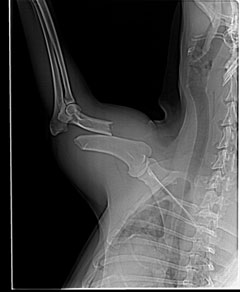

Unsere Tierschützer in Portugal wurden informiert, dass ein Hund an einer Schnellstrasse überfahren wurde. Sie fuhren hin und sahen Klaus-Dieter hilflos am Strassenrand liegen. Er wollte aufstehen, aber er konnte nicht. Sein rechtes Hinterbein und sein rechtes Vorderbein waren gebrochen. Klaus Dieter wurde von rücksichtslosen Autofahrern erfasst und einfach liegen gelassen.

Wir entschieden natürlich sofort, ihn operieren zu lassen, damit ihm die Schmerzen genommen werden. Klaus-Dieter hat die OP prima überstanden, alles verläuft bestens und er wird wieder normal laufen können.